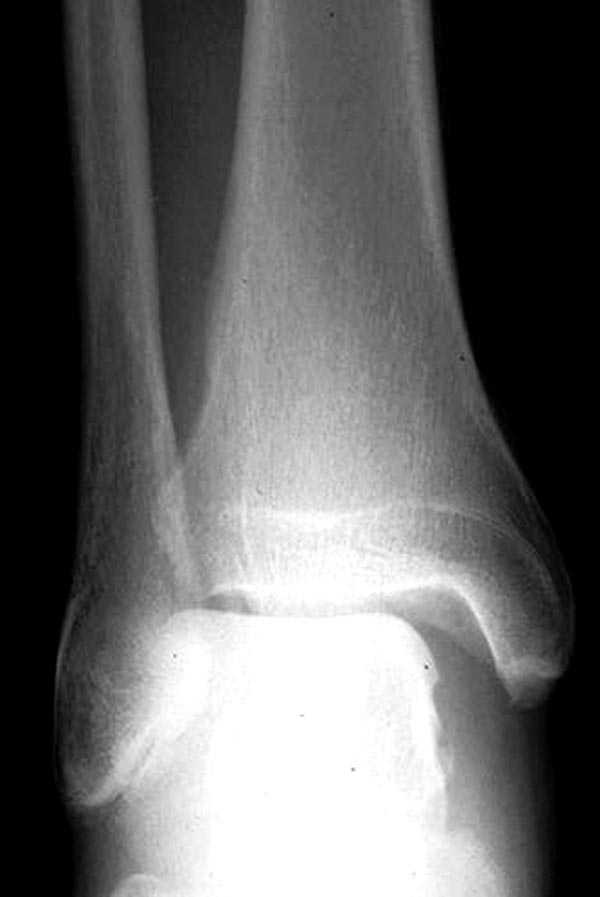

Здесь как раз тот случай, когда рентгеновский снимок скрывает главную проблему. "Ходит, прихрамывая на правую ногу, отмечает боли в правом голеностопном суставе" По описанию клиника типичная для повреждения голонестопного сустава - синдесмоза.

На прямой проекции можно увидеть расширенную медиальную щель, и на мортизе укорочение малоберцовой.

Невозможно устранить проблему фиксацией малоберцовой пластиной или другими методами, потому что главная проблема - разрыв межберцовой мембраны, которая находится между костями и внизу в голеностопе в синдесмозе.